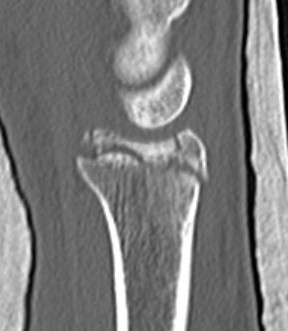

CT

Radial styloid + dorsal rim fractures